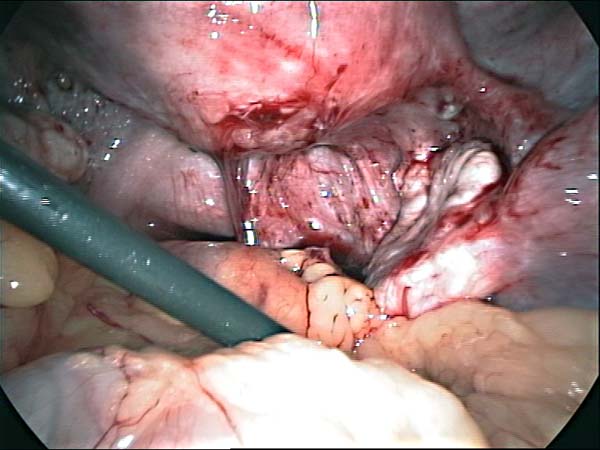

- Laparoscopy Photos 1

- Laparoscopy Photos 2

- Laparoscopy Photos 3

- Laparoscopy Photos 4

Laparoscopy Photos Polycystic Ovaries adhesiolysis IUCD Through Uterine Wall | Dr N Layyous